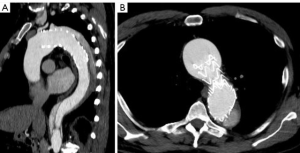

He had several follow-up computed tomography (CT) scans that showed a type 1A endoleak originating in the arch and an associated “bird-beak” configuration of the stent-graft. The aortic arch aneurysm proximal to the endograft had also been slowly growing, measuring 6.2 cm × 6.0 cm in diameter (Figure 2). The residual aortic dissection extended from the level of the left subclavian artery into the left external iliac artery. The size of the dissected mid-descending aorta measured 5.2 cm × 4.6 cm and has been relatively stable. His aortic root was also dilated measuring 4.5 cm. Transthoracic echocardiography demonstrated a tricuspid aortic valve with mild aortic insufficiency and normal biventricular function. In preparation for surgical repair, he underwent coronary angiography that was unremarkable. He was recommended to undergo elective aortic root, ascending and total arch replacement with a modified branched frozen elephant trunk repair to include stent grafting into the left subclavian and left carotid arteries. It was also explained that this may be the first of a staged repair approach to his extensive dissection disease.